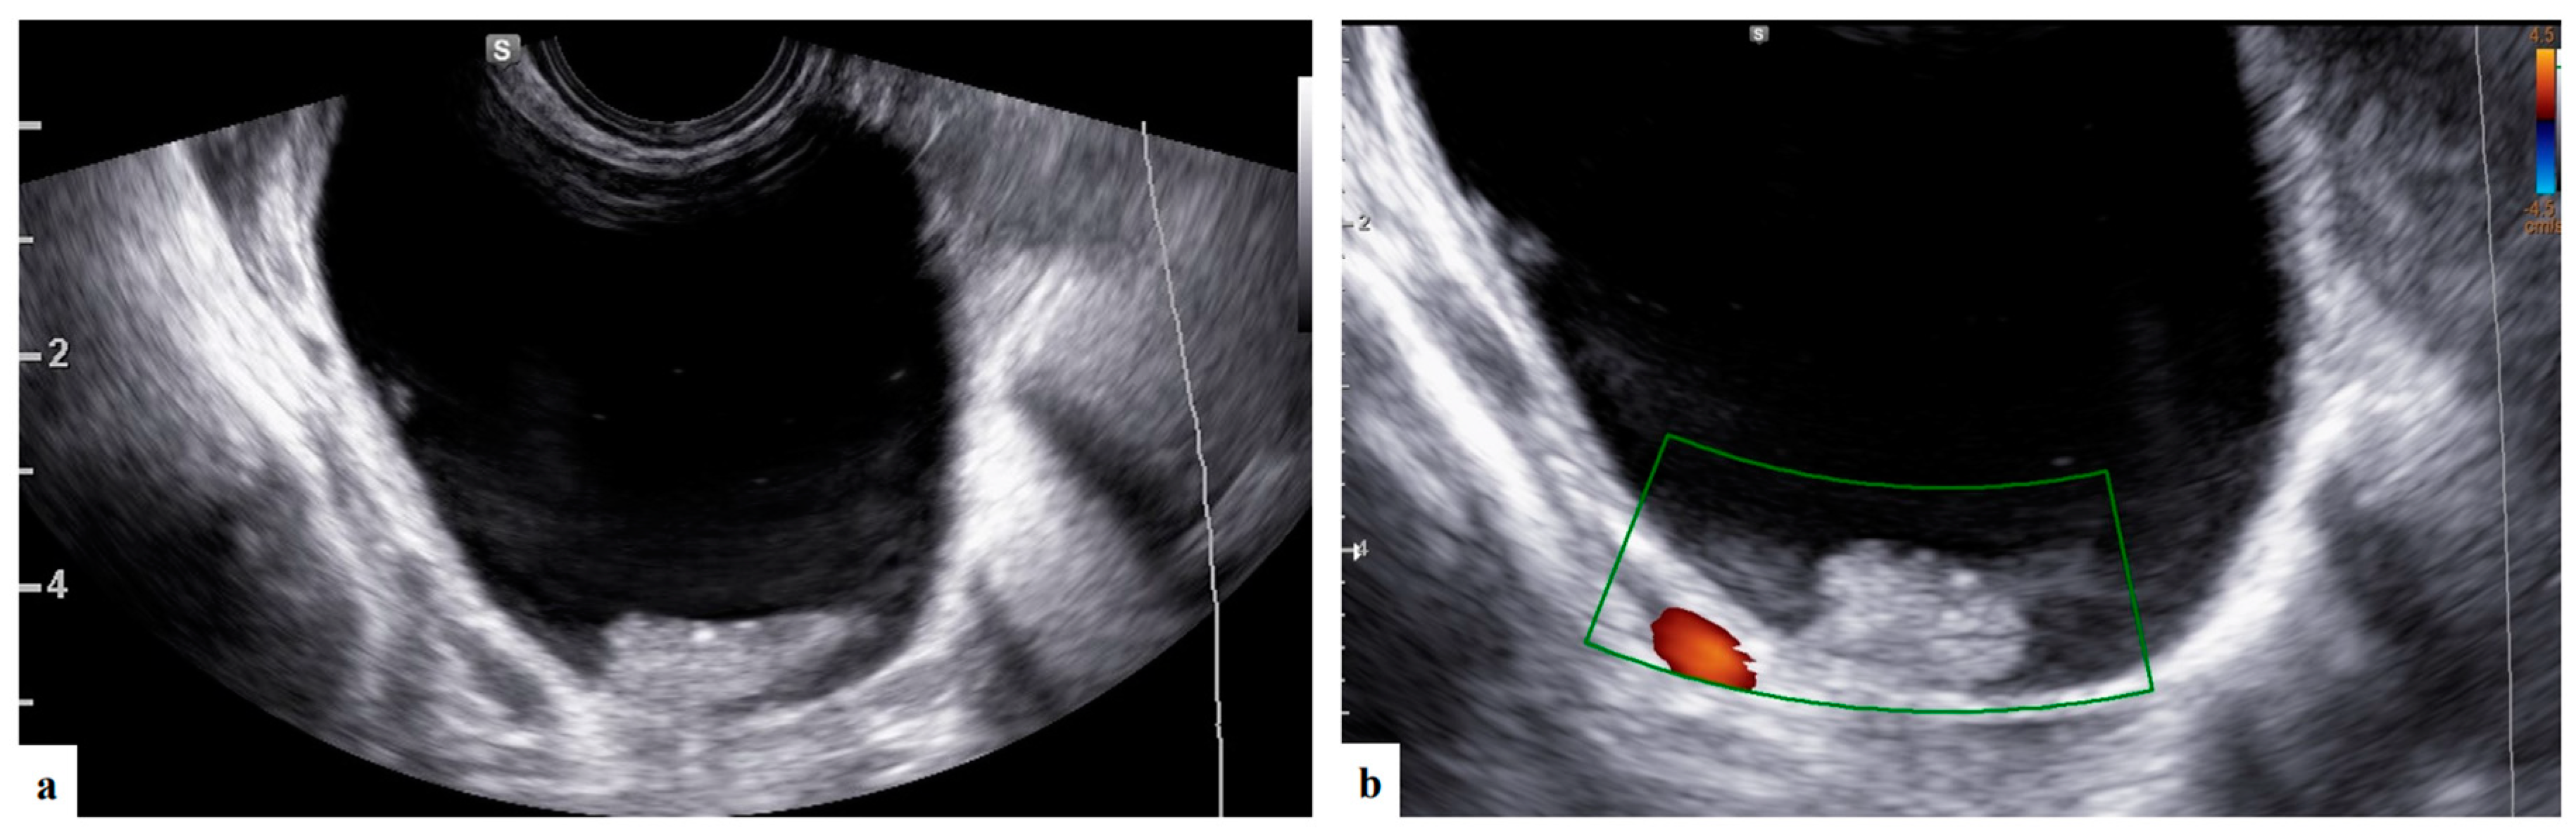

- Mascilini, F.; Moruzzi, C.; Giansiracusa, C.; Guastafierro, F.; Savelli, L.; De Meis, L.; Epstein, E.; Timor-Tritsch I., E.; Mailath-Pokorny, M.; Ercoli, A.; Exacoustos, C.; Benacerraf B., R.; Valentin, L.; Testa, A.C. Imaging in gynecological disease. 10: Clinical and ultrasound characteristics of decidualized endometriomas surgically removed during pregnancy. Ultrasound Obstet Gynecol 2014, 44, 354–360. [Google Scholar] [CrossRef]

| Presence of papillary projections | 4 |

| Number of papillary projections 1 2 3 |

1/4 2/4 1/4 |

| Papillation contour Irregular Smooth |

1/4 3/4 |

| Papillation flow Present Absent |

2/4 2/4 |

| Heigh of the largest papillary projection (mm) (range) | 7.5 (3-13) |